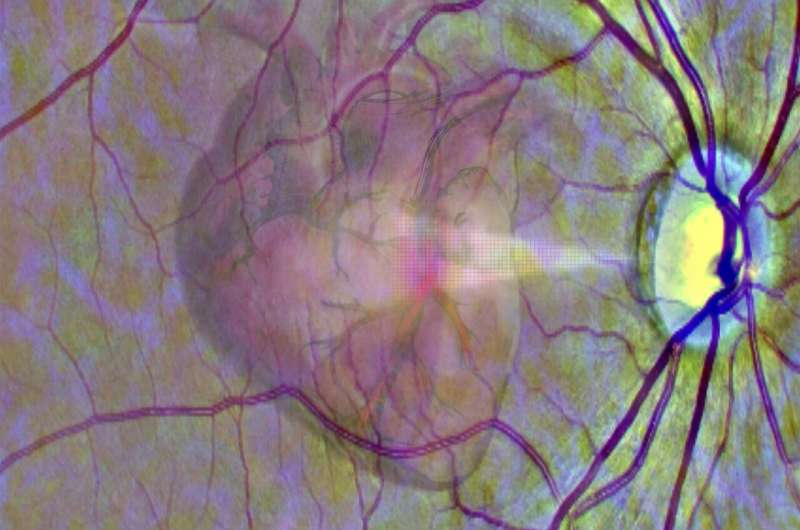

Using the eye as a window into heart disease #eyescan #heartdisease #AI For more information | ⬇️ buff.ly/3H6CKcU

Cn1699's tweet image. Using the eye as a window into heart disease

#eyescan #heartdisease #AI

For more information | ⬇️

buff.ly/3H6CKcU

Scientists at @UniversityLeeds, @NIH & Chinese Academy of Sciences made an #AI that can identify #heartdisease from #eyescan. Now patients at high risk of future myocardial infarction can be identified from retinal imaging. #news #scicomm #ML #techtwitter nature.com/articles/s4225…

SaurabhGayali's tweet image. Scientists at @UniversityLeeds, @NIH & Chinese Academy of Sciences made an #AI that can identify #heartdisease from #eyescan. Now patients at high risk of future myocardial infarction can be identified from retinal imaging. #news #scicomm #ML #techtwitter nature.com/articles/s4225…